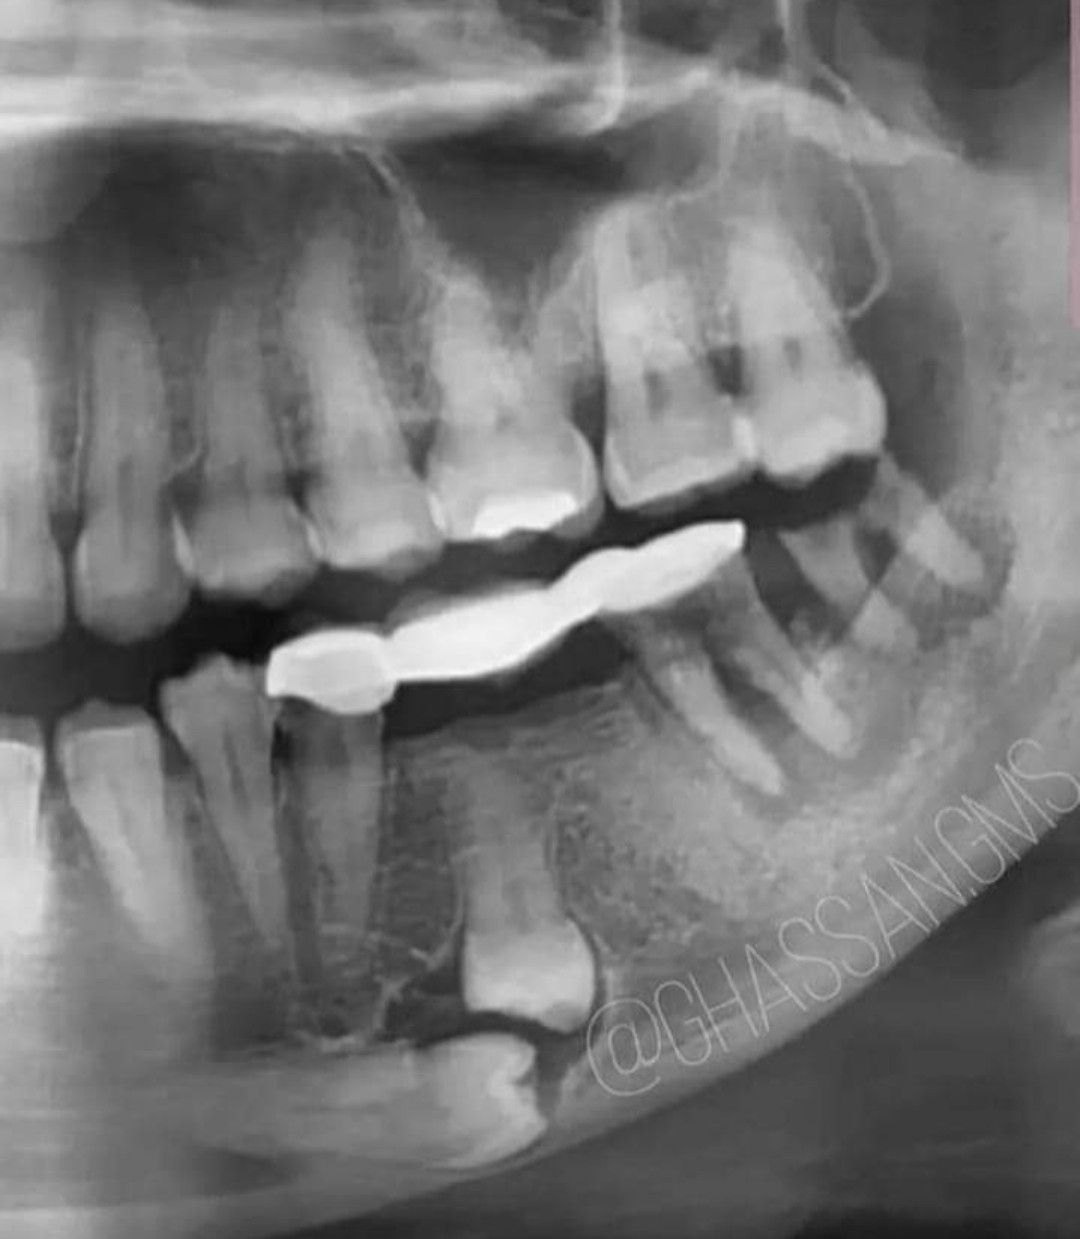

Anesthesia for Extraction

Should these teeth be extracted under GA or LA?